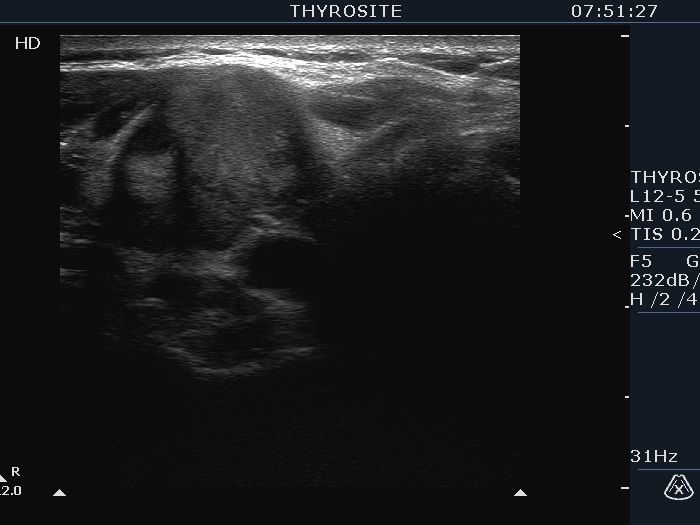

Ultrasonography. The thyroid was echonormal and had multiple nodules. The largest lesion in the right lobe was minimally hypoechoic had irregular borders and presented all three possible signs of an extrathyroidal spread. The vascularity was scanty. The largest nodule in the left lobe was also remarkable due to numerous echogenic lines and granules which were related to ventral cystic areas. So, these were back wall figures.